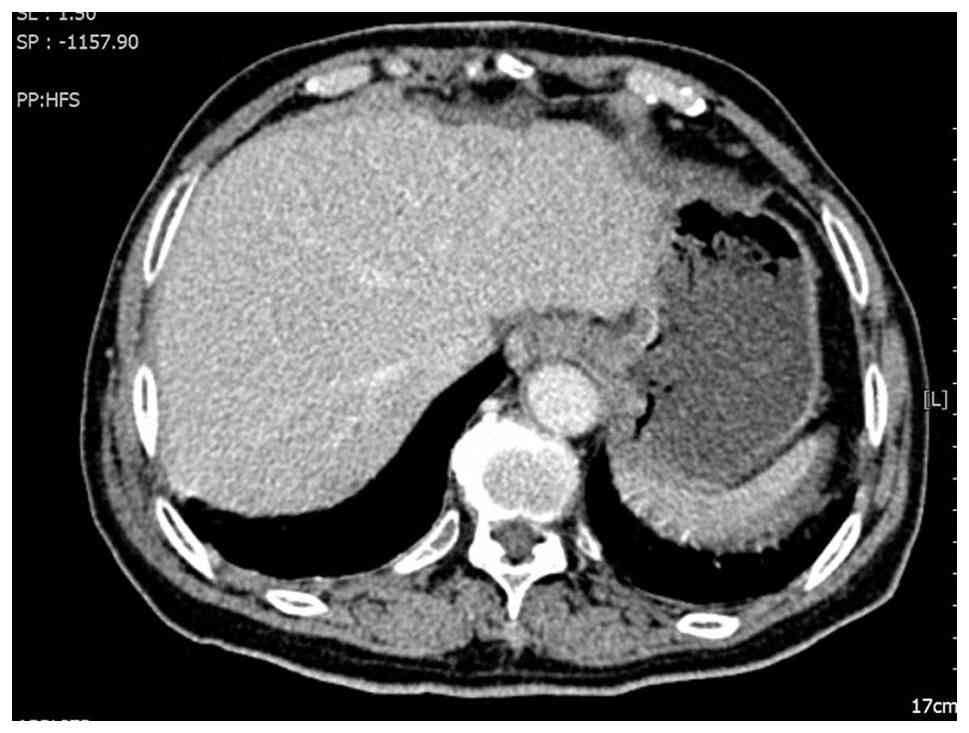

A 78-year-old woman was admitted to Suining Central Hospital (Suining, China) in June 2013 presenting with repeated bloody stools for >1 month that had worsened 1 day prior to admission. An abdominal CT scan upon admission revealed wall thickening at the rectosigmoid junction and enlargement of the perirectal and bilateral inguinal lymph nodes, raising suspicion of a malignant tumor (Fig. 1A and B). The medical team recommended a colonoscopy for further diagnostic clarification. After being informed of the risks and benefits of the procedure, the patient declined colonoscopy and requested direct surgical intervention. Following a multidisciplinary team discussion, it was concluded that the probability of colon cancer was high and that proceeding directly to surgical exploration was appropriate given the patient's refusal of a colonoscopy. The patient underwent laparoscopic radical surgery for rectal cancer under general anesthesia 2 days after admission. Tissues were fixed in 10% neutral buffered formalin at 15–25°C for 12–24 h and then sectioned to 4-µm thick. Hematoxylin and eosin staining was used at 15–25°C for 45 min, and the results were assessed under an Olympus BX43 optical microscope (Olympus Corporation). The postoperative pathological diagnosis confirmed a moderately to well-differentiated ulcerative adenocarcinoma (Fig. 1C), but the patient subsequently declined adjuvant chemotherapy. A follow-up abdominal CT scan 3 months after surgery demonstrated multiple liver nodules, suggesting the presence of metastatic tumors (Fig. 2).

Preoperative computed tomography scan

and postoperative pathological. (A) Thickening of the intestinal

wall at the junction of the sigmoid colon and rectum (arrow). (B)

Enlarged perirectal lymph nodes (arrow). (C) Postoperative

pathology reveals moderately to well-differentiated ulcerative

adenocarcinoma (H&E staining; ×400 magnification). H&E,

hematoxylin and eosin.

Figure 1.

Preoperative computed tomography scan and postoperative pathological. (A) Thickening of the intestinal wall at the junction of the sigmoid colon and rectum (arrow). (B) Enlarged perirectal lymph nodes (arrow). (C) Postoperative pathology reveals moderately to well-differentiated ulcerative adenocarcinoma (H&E staining; ×400 magnification). H&E, hematoxylin and eosin.